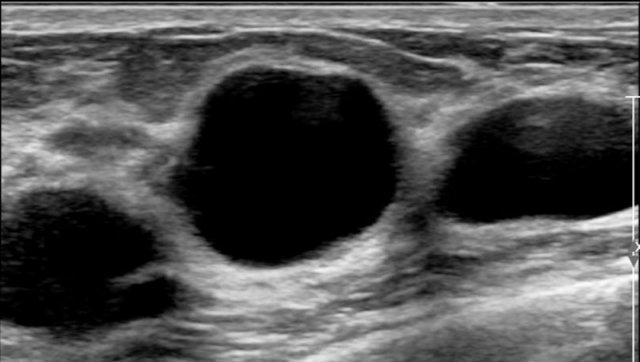

Đây là một ví dụ điển hình về nhiều nang ở một phụ nữ có khối u sờ thấy được ở vú.

Mặc dù có nhiều nang, nhưng chỉ có nang ở trung tâm mới sờ thấy được, vì nang này có hình tròn với dịch chịu áp lực căng bên trong.

Các nang còn lại không sờ thấy được, vì chúng có cảm giác tương tự như mô vú bình thường xung quanh.

Việc phát hiện thêm nhiều nang ở một phụ nữ đến khám vì có nang sờ thấy được là điều rất thường gặp.